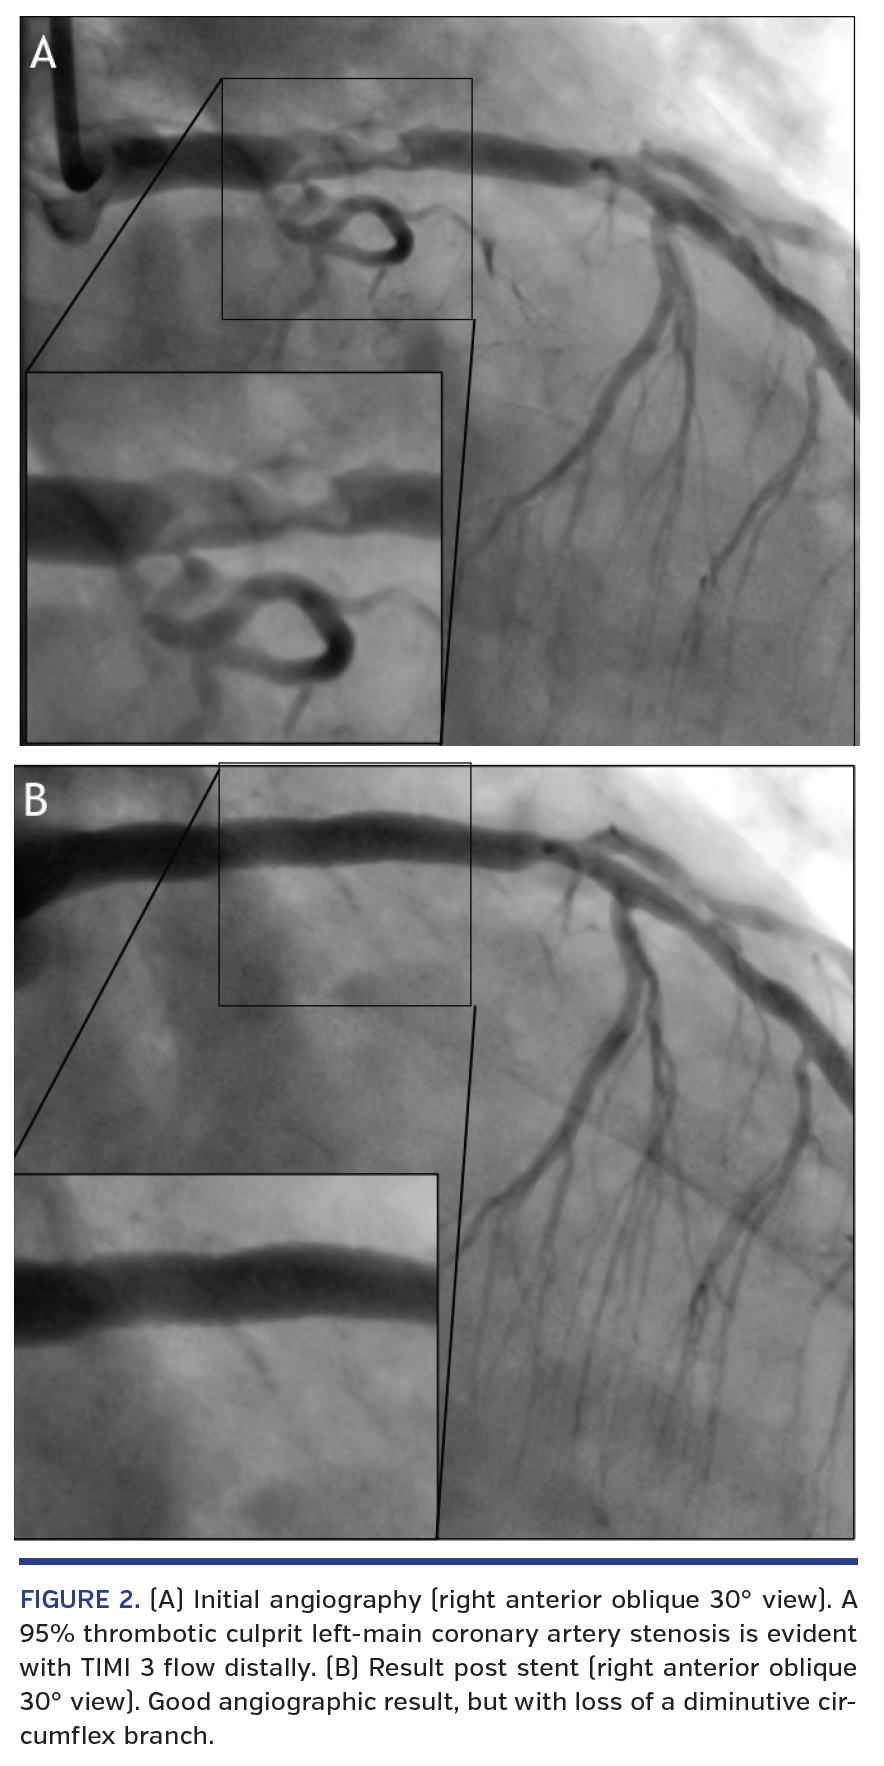

Twenty minutes after thrombolysis, there was >50% (but not complete) ST-segment resolution (Figure 1B), with ongoing but lessening pain, such that the patient was then taken immediately to the cardiac catheterization laboratory, with a total door-to-needle time of 62 min. Angiography revealed a 95% thrombotic culprit LM stenosis with TIMI 3 flow distally (Figure 2A), and a very distal right coronary artery lesion (not shown). The culprit was stented uneventfully except for asymptomatic loss of a diminutive circumflex branch (Figure 2B). An intra-aortic balloon pump was not deployed given improved hemodynamics and chest pain resolution at the end of the procedure. Hematemesis occurred within 24 hr secondary to Mallory-Weiss tear. There was a short period on inotropes including levosimendan, with an initial ejection fraction estimated at 35%, after which there was a return to mild left ventricular dysfunction only (echo ejection fraction, 45%). At 3 months, the patient is playing 18 holes of golf daily, and is asymptomatic on medical therapy.